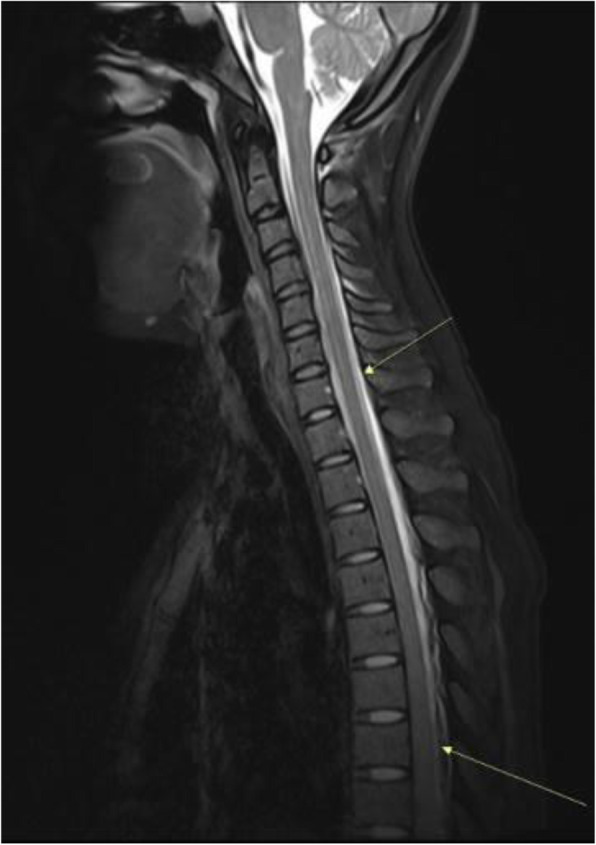

Background and purpose: Although the majority of migraine with aura (MwA) patients experience simple visual aura, a discrete percentage also report somatosensory, dysphasic or motor symptoms (the so-called complex auras). The wide aura clinical spectrum led to an investigation of whether the heterogeneity of the aura phenomenon could be produced by different neural correlates, suggesting an increased visual cortical excitability in complex MwA. The aim was to explore whether complex MwA patients are characterized by more pronounced connectivity changes of the visual network and whether functional abnormalities may extend beyond the visual network encompassing also the sensorimotor network in complex MwA patients compared to simple visual MwA patients.

Methods: By using a resting-state functional magnetic resonance imaging approach, the resting-state functional connectivity (RS-Fc) of both visual and sensorimotor networks in 20 complex MwA patients was compared with 20 simple visual MwA patients and 20 migraine without aura patients.

Results: Complex MwA patients showed a significantly higher RS-Fc of the left lingual gyrus, within the visual network, and of the right anterior insula, within the sensorimotor network, compared to both simple visual MwA and migraine without aura patients (p < 0.001). The abnormal right anterior insula RS-Fc was able to discriminate complex MwA patients from simple aura MwA patients as demonstrated by logistic regression analysis (area under the curve 0.83).

Conclusion: Our findings suggest that higher extrastriate RS-Fc might promote cortical spreading depression onset representing the neural correlate of simple visual aura that can propagate to sensorimotor regions if an increased insula RS-Fc coexists, leading to complex aura phenotypes.

Fig. 1 (abstract A20).

See text for description.